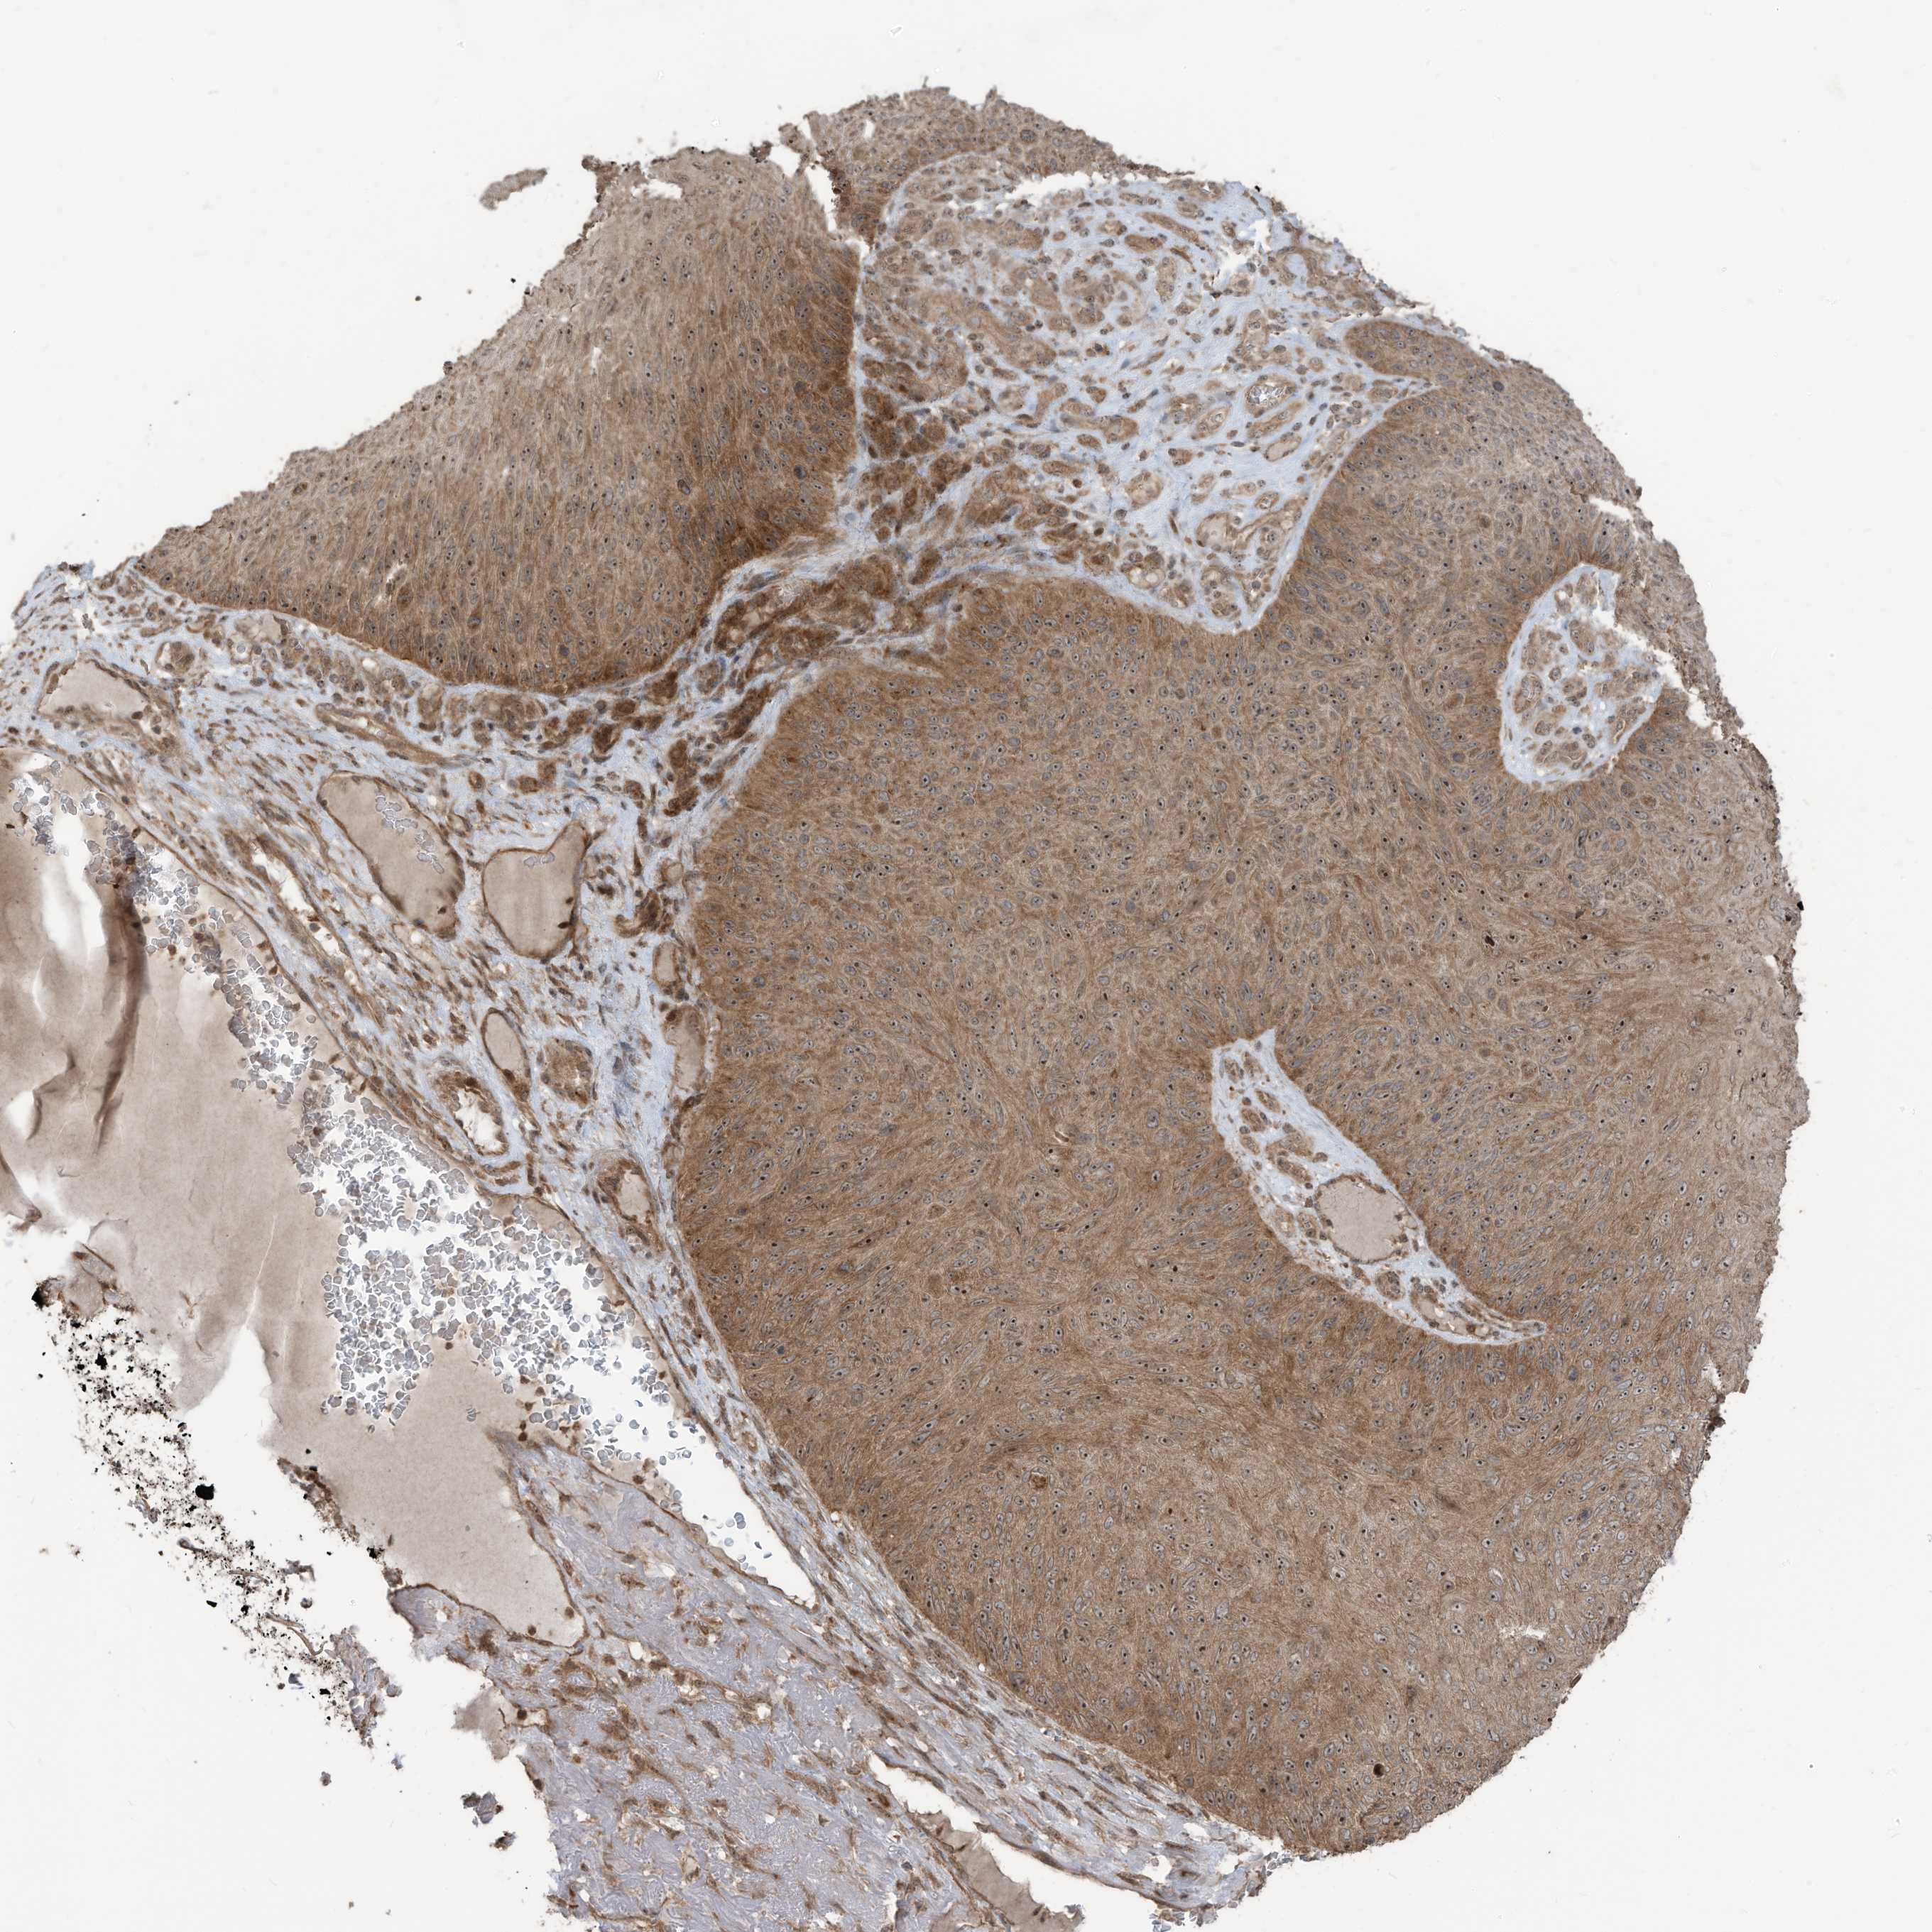

SKIN CANCER - Protein expressioni

A mouse-over function shows sample information and annotation data. Click on an image to view it in a full screen mode. Samples can be filtered based on level of antibody staining by selecting one or several of the following categories: high, medium, low and not detected. The assay and annotation is described here.

Antibody stainingi

Antibody staining in the annotated cell types in the current human tissue is reported as not detected, low, medium, or high, based on conventional immunohistochemistry profiling in selected tissues. This score is based on the combination of the staining intensity and fraction of stained cells.

Each image is clickable and will lead to virtual microscopy that enables deeper exploration of all samples and also displays staining intensity scores, fraction scores and subcellular localization as well as patient and tissue information for each sample.

Antibody HPA034557

Staining

High

Medium

Low

Not detected

Intensity

Strong

Moderate

Weak

Negative

Quantity

>75%

75%-25%

<25%

None

Location

Nuclear

Cytoplasmic/membranous

Cytoplasmic/membranous,nuclear

Squamous cell carcinoma, NOS